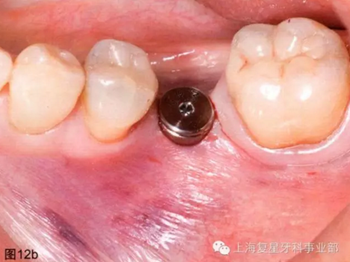

通過導(dǎo)板的引導(dǎo),以15prm,50Ncm旋入種植體。一旦種植體到達(dá)最后的深度(圖12a),去除種植手機(jī)和攜帶器,然后將一個(gè)愈合基臺(tái)(BioHorizons,直徑4.5毫米×長3毫米)擰在種植體上(圖12b)。軟組織打孔器取出的軟組織進(jìn)行結(jié)締組織移植,然后放置在一個(gè)頰楔上獲得一定體積和厚度的角質(zhì)化軟組織(圖12c)。無需縫合。術(shù)后拍攝X片,對種植體的最終位置進(jìn)行評(píng)估。

圖12b:已放入愈合基臺(tái)